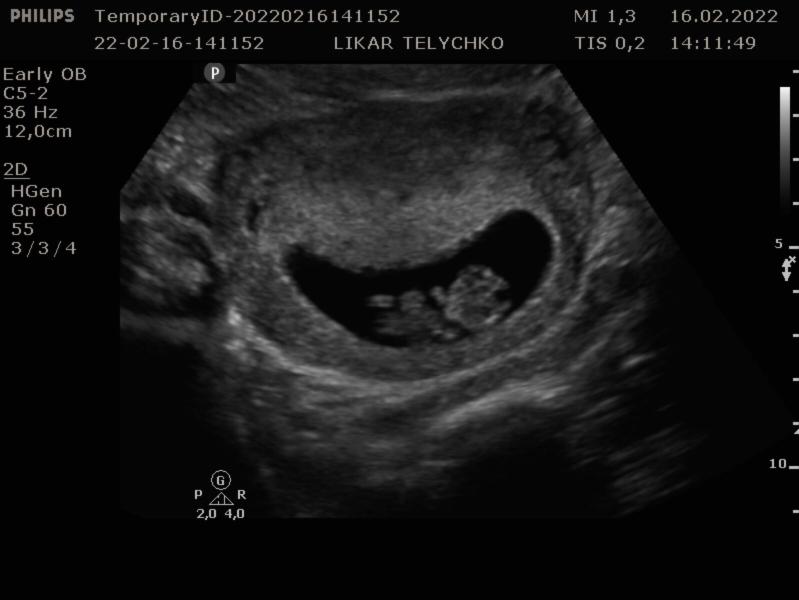

Була вчора на узі 🙏 минулого разу це були три цяточки , а тепер я вже бачила там дитинку , ми вже такі великі🙏🙏🙏 наша ляля махала нам ручками , активнічала дуже ❤️❤️❤️🥰🥰🥰 нашому щастю немає меж 🙏